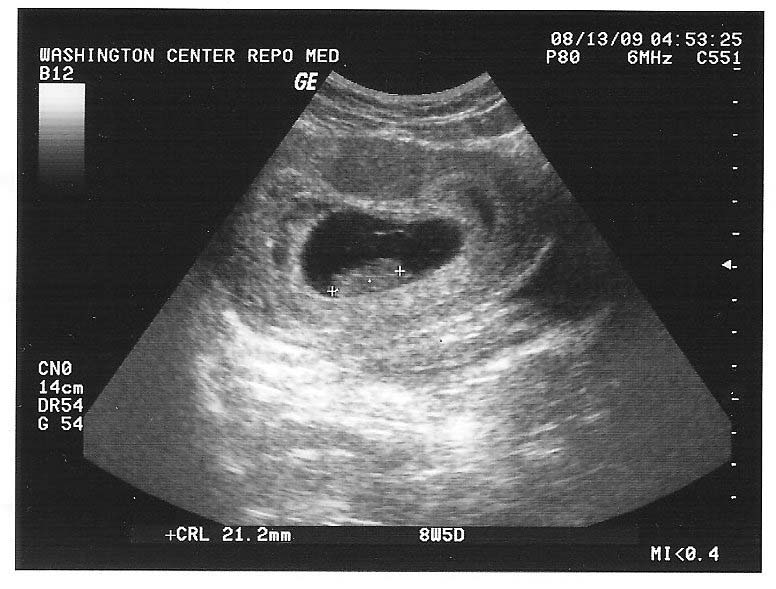

I suppose it was more intense because we were just thinking, ‘We hope you hang around’. There was real excitement, but it was really intense. Some conditions can’t be seen on a scan at all or can’t be seen until later in the pregnancy.īecause of the first miscarriage, we went for an eight-week scan. If there are medical concerns, or you’ve had problems with a previous pregnancy, or if there’s too much uncertainty about the dates of the pregnancy, your doctor might suggest extra scans or tests. As well as taking care of her, it’s important to recognise your own feelings and talk with someone you trust. If this is the case, your partner will need your support. There’s also a chance that the scan might pick up other health problems or complications. Along with grief and disappointment, you might feel helpless at not being able to protect your partner or your baby. Around 10-25% of pregnancies are miscarried, and 80% of miscarriages happen before 12 weeks. Miscarriage or health problems at 12 weeksĪlthough most pregnancies are straightforward and progress without problems, there’s a chance the scan could show that your baby is no longer alive.Ī miscarriage is when a baby dies before 20 weeks of pregnancy. If you’re thinking about having these tests, genetic counselling services can give you more information about them.

You won’t be able to find out the sex of your baby yet. You’ll hear baby’s heartbeat and might even see some hand-waving or acrobatics. It’s when you see your baby for the first time.

If everything is OK, this scan is likely to be one of the most amazing moments of your life. is part of the check on the chance of your baby having a condition like Down syndrome.helps health professionals work out your baby’s age and estimated due date.checks that your baby is developing as expected.checks that your baby is growing in the right place – that is, inside the womb.Your partner will be offered her first ultrasound scan at 6-12 weeks of pregnancy.